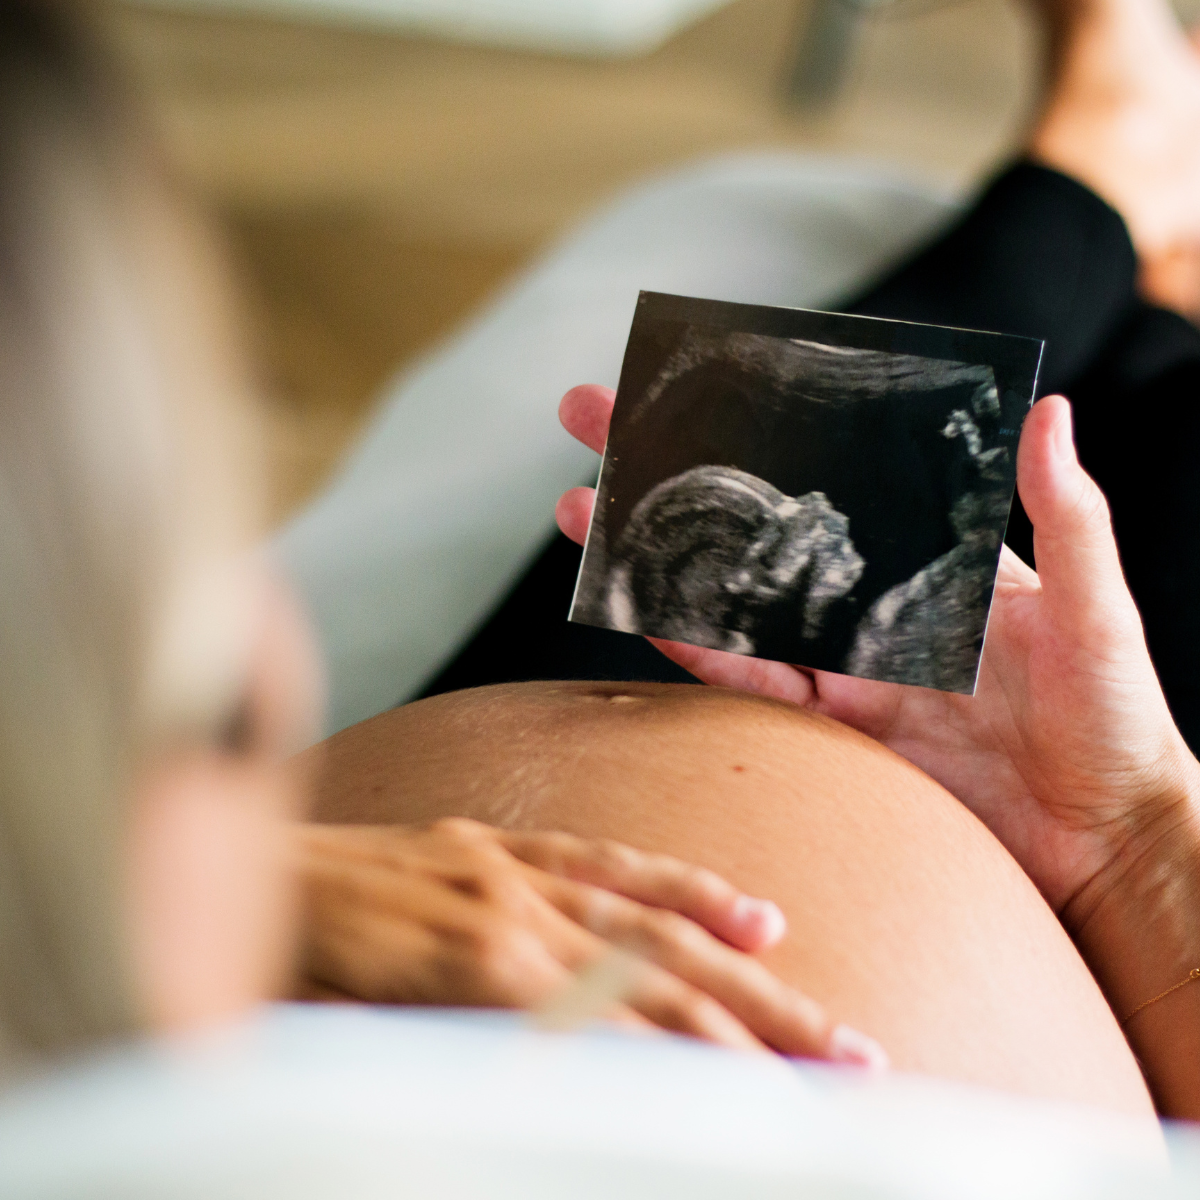

Realizarlo entre las 11 a 14 semanas ( ideal 12 semanas)

Las primeras semanas son muy importantes para ti y para tu bebé, en la actualidad se considera una de las evaluaciones ultrasonográficas más importantes durante el embarazo.